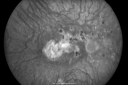

Disciform Scar after Photodynamic Laser - Macular Hemorrhage and Vitrectomy828 views84-year-old man has age-related macular degeneration in both eyes, with a disciform scar in the right eye. He had a subfoveal hemorrhage in that eye treated with vitrectomy and displacement on May 3, 2006. He previous to that had photodynamic laser. These photos are from October 2010. VA is 1/200.